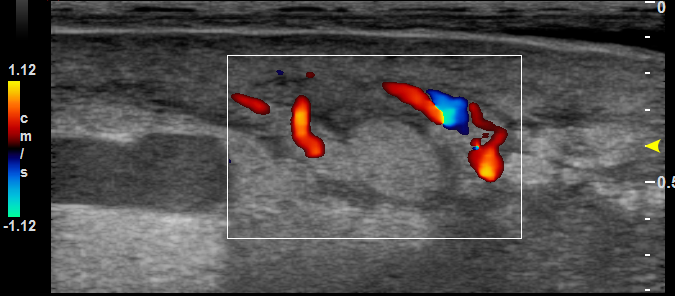

超高频超声:可视化显示淋巴管腔内移动的淋巴液和功能瓣膜,识别前臂掌侧和背侧、小腿内侧等的功能性淋巴管(包括直径小于0.3mm的淋巴管),淋巴管直径测量较高频超声小且精确。

可用于淋巴-静脉吻合术前定位(缩短手术时间,治疗淋巴水肿)。

穿支血管

血流速度